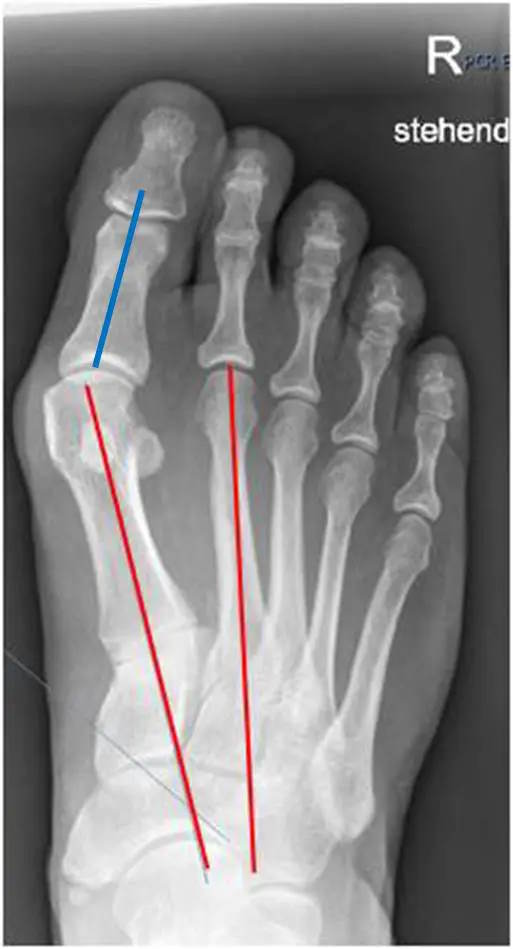

Die bildgebende Diagnostik umfasst ein Röntgenbild im dorso-plantaren Strahlengang des belasteten Fußes. Auf der dorso-plantaren belasteten Aufnahme können der Winkel zwischen dem Metatarsale I und II (Intermetatarsal Winkel) und der Winkel zwischen Metatarsale und Großzehe (HV Winkel) bestimmt werden. Zudem können die Kongruenz des Großzehengrundgelenkes bzw. die Stellung der Sesambeine beurteilt werden. Weitere Aufnahmen sind in der Regel nicht erforderlich. Schrägaufnahmen oder schnittbildgebende Verfahren wie eine MRT oder CT Untersuchung bleiben besonderen Fragestellungen vorbehalten.

Röntgenbild Fuß rechts, d.p. Strahlengang im Stand: rot-rot: Intermetatarsal Winkel, rot-blau: HV Winkel